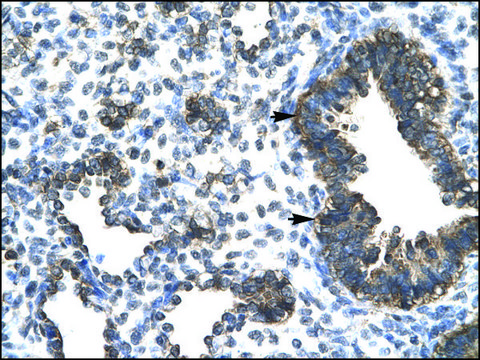

Rabbit ESRRG antibody has been used for co-immunoprecipitation and western blot assays. Sigma has verified the use of the product in western blot (0.5μg/ml) and immunohistochemistry (4-8μg/ml, using paraffin-embedded tissue sections) applications.